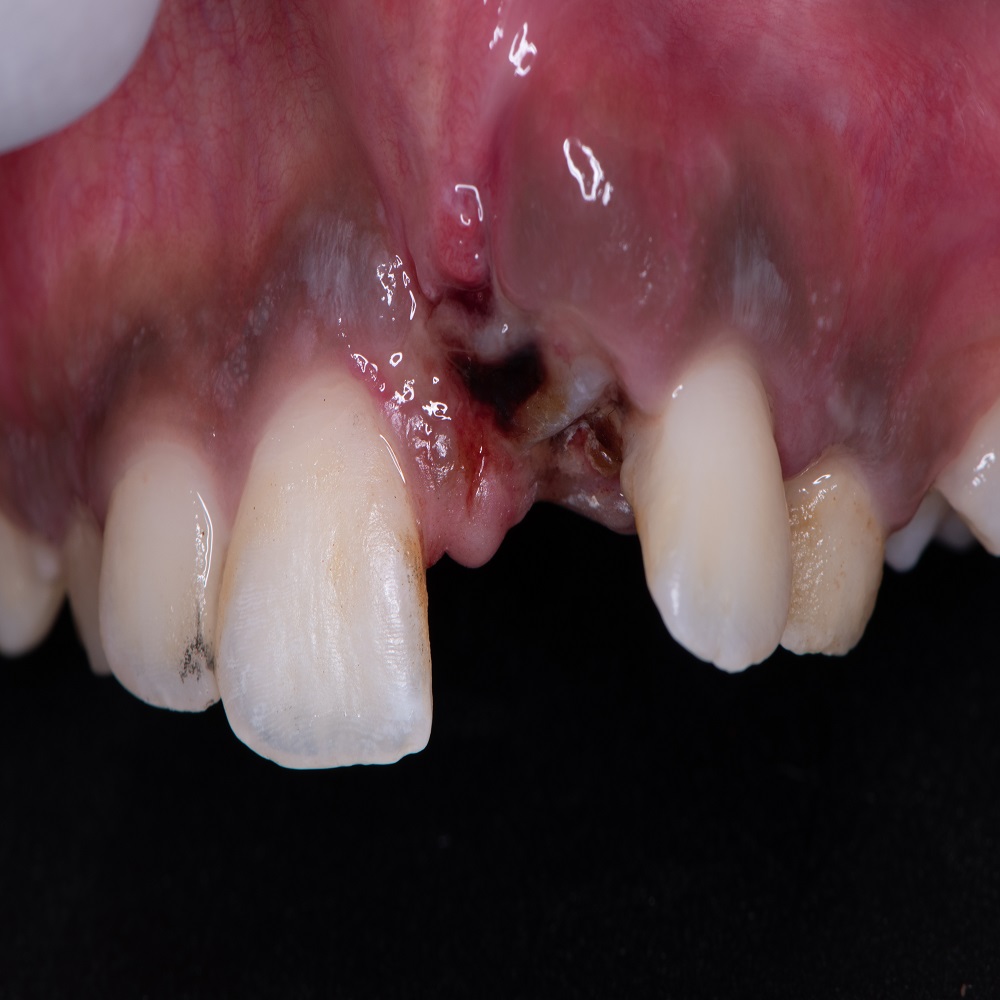

- E-Book published on Contemporary Understanding of Management of Avulsed Tooth (Lambert Academic Publishing) on 5th February 2025.